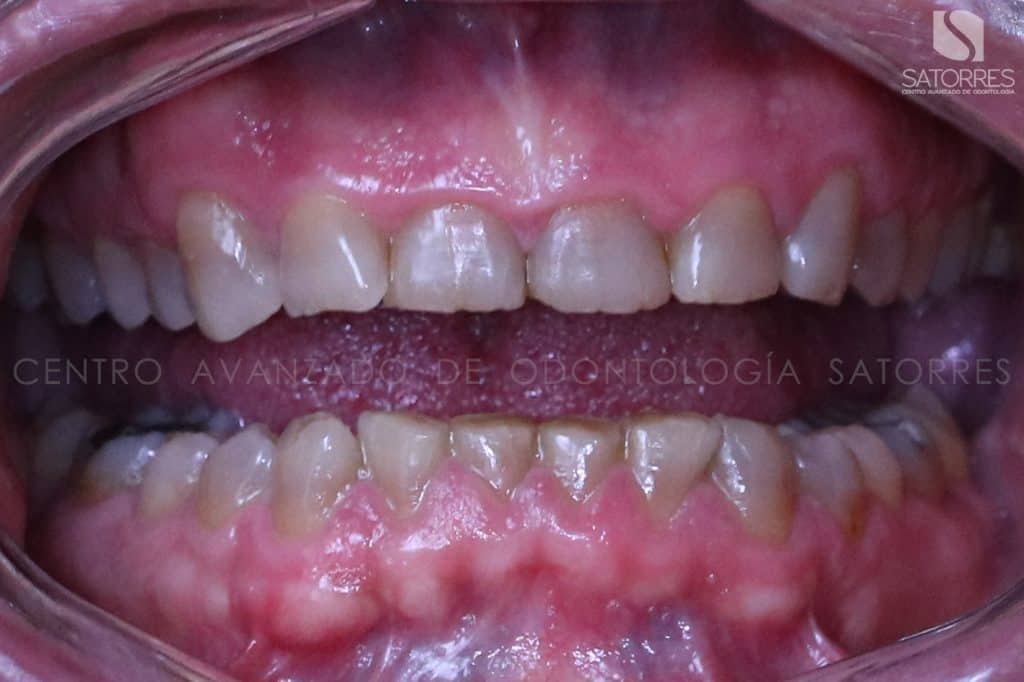

El cambio de sonrisa de uno de nuestros pacientes

Veamos el proceso de uno de nuestros pacientes y el resultado que tuvo con este tratamiento de estética dental.

El paciente llega al Centro Avanzado de Odontología Satorres queriendo mejorar la estética de sus dientes.

Lo primero que se le realiza es un estudio completo de su sonrisa para ver la funcionalidad, la simetría y las posibilidades de estética de la misma.